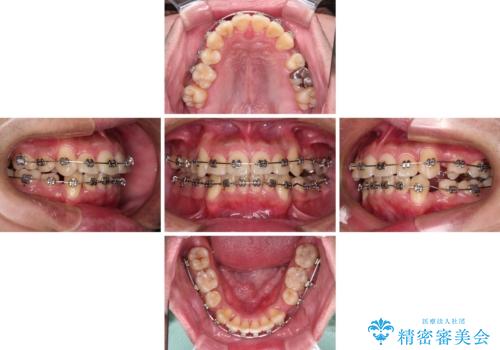

デコボコと口元の突出感を改善 抜歯矯正治療

- メタルブラケット

- 3年10ヶ月

- 30回以上

右上第一小臼歯は歯根癒着により移動せず、左上第二小臼歯は移動はするものの非常に動きが鈍かったため、抜歯したスペースを閉じるまでに非常に時間がかかってしまいました。

患者様には辛抱強く治療にお付き合いいただき、すっきりとした口元に仕上げることができました。